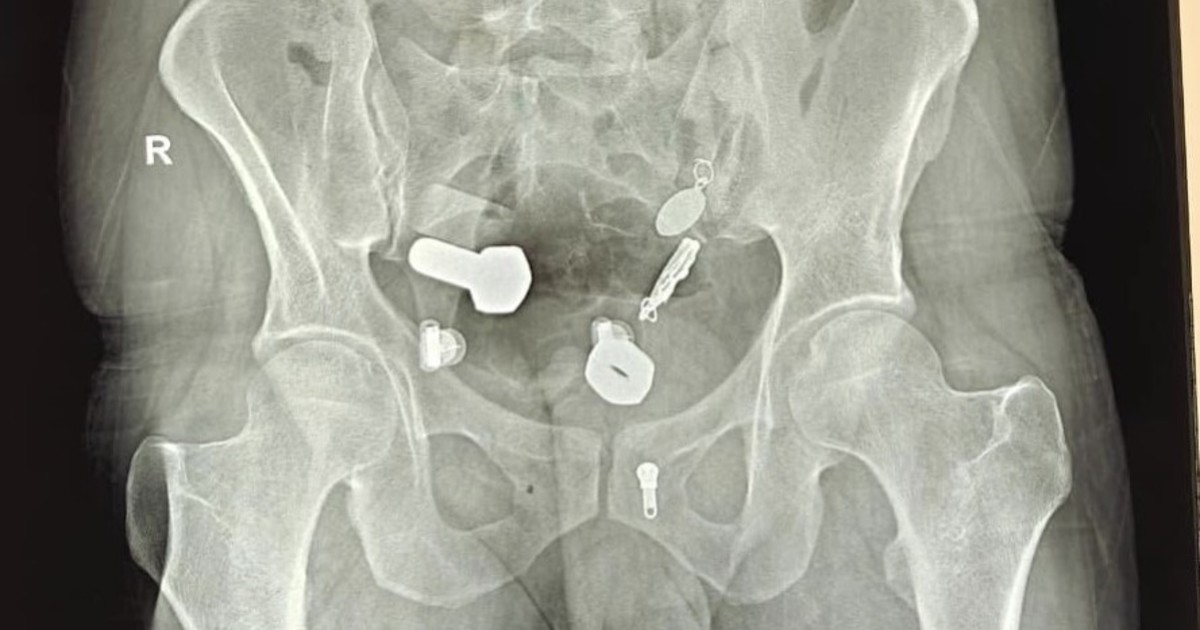

En una clínica de la India, médicos hicieron un impactante hallazgo adentro del cuerpo de un paciente. El hecho ocurrió en la ciudad de Jaipur.